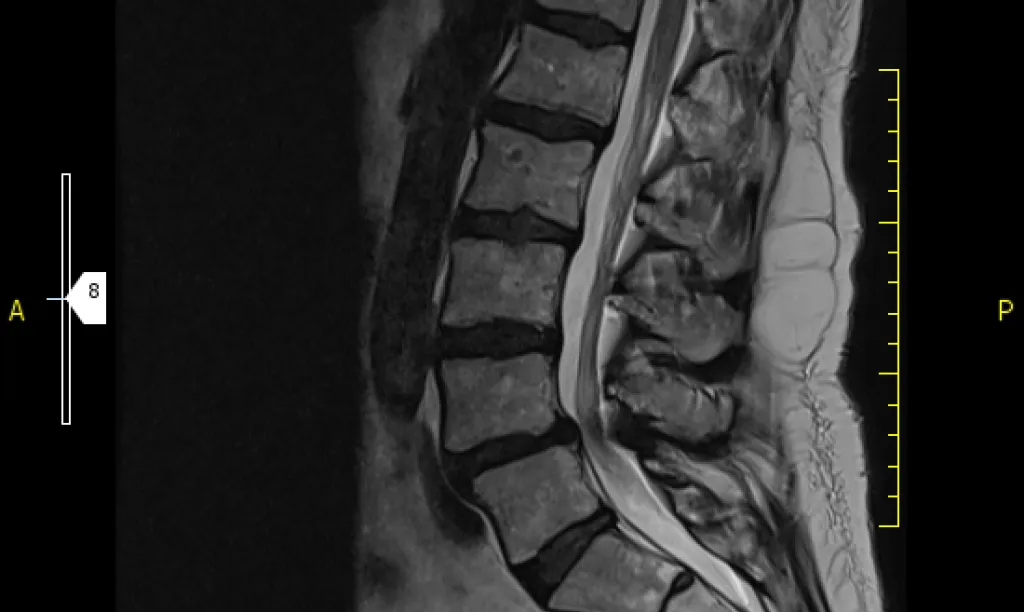

La Resonancia Magnética de columna (cervical, dorsal o lumbar) es la prueba de elección para valorar discos intervertebrales, vertebral y médula.

La Resonancia Magnética es la técnica más precisa para valorar estructuras neurológicas que incluye médula y raíces nerviosas así como la valoración de la hidratación de los discos intervertebrales y su degeneración.

1. Lesiones discales: abombamientos, protrusiones y hernias entre otras

2. Lesiones de articulares: hipertrofia facetas articulares

3. Compresiones nerviosas o medulares: estenosis de canal